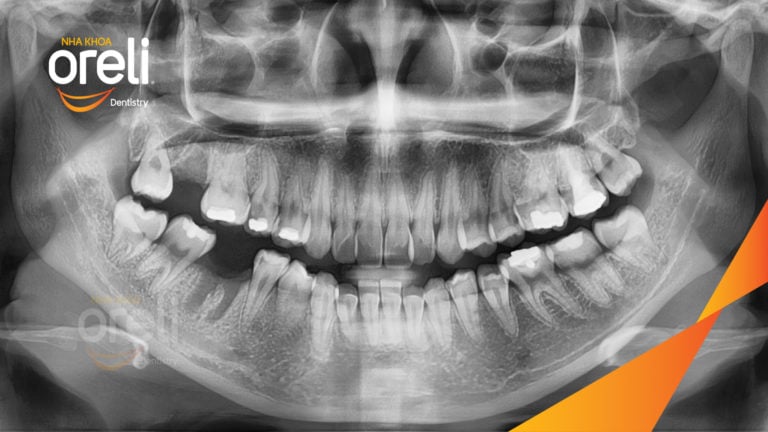

Ca niềng răng đặc biệt: kéo răng 7, 8 thay thế 3 răng 6 bị hư tại Oreli Niềng răngDi gần răng 7 8 Xem thêm